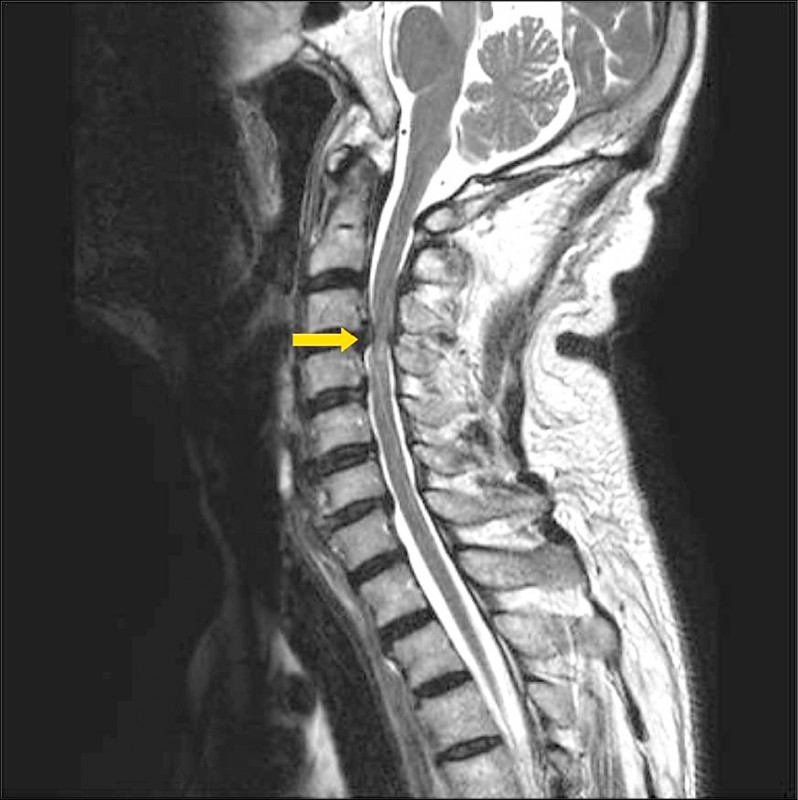

Feb 26, 21 · 颈椎压迫神经的症状分为压迫神经根和颈髓两方面。 颈椎压迫神经根的症状有:1、疼痛,一般表现为自颈部向上肢的放射性疼痛;2、感觉障碍,受到压迫神经根在上肢的支配区出现麻木、痛觉过敏、感觉减退等症状;3、肌力改变,早期肌张力亢进,晚期肌张力减弱,肌肉出现萎缩。Nov 08, 11 · 颈椎病吃药只是缓解作用,要除根的话建议您还是接受正规的治疗,最好是保守治疗,您与眩晕的情况的话应该属于脊髓型的,最好不要再耽误了,我们是通过中医手法复位正骨后(正骨12周,每隔一天一次,30分钟每次)改变压迫神经的关节位置使其不再压迫Aug 23, 19 · 虽然说确实有压迫神经的可能,但依然只是猜测,目前已有的检查并不能确诊! 患者需要做一个颈部核磁,这个检查是很有必要的,不光是确诊,更是未来治疗的依据,我们需要通过核磁更为详细的了解患者病情,病变位置、神经压迫程度进行综合考虑,对于此类患者来说,治疗方式有很多,作

颈椎影响到手臂疼痛什么药也不吃,除了让你花钱没有别的任何作用颈椎病引起的手麻 手肿涨 手疼 胳膊肿涨疼痛 疼痛感减弱的原因是颈椎5,6错位挤压了颈椎神经和血管造成的治疗方法是1用大拇指按压住颈椎的疼痛点,颈椎右侧疼痛Nov 27, · 口服药物也是治疗颈椎病很好的方法,常用的药物有止痛药、肌松药、营养神经的药物以及脱水药。 "郑帅表示,通过以上方案的综合治疗,一般的Mar 24, 21 · 早期颈椎病保守治疗,当出现了肌肉无力、萎缩,影像学检查显示病变节段颈椎间盘突出或椎体后缘、钩椎关节骨骜形成,压迫神经根或硬膜囊者,通常就考虑手术治疗。 颈椎微创手术创伤小、康复快,脊柱内镜可以清晰地辨别神经组织和血管等细微结构